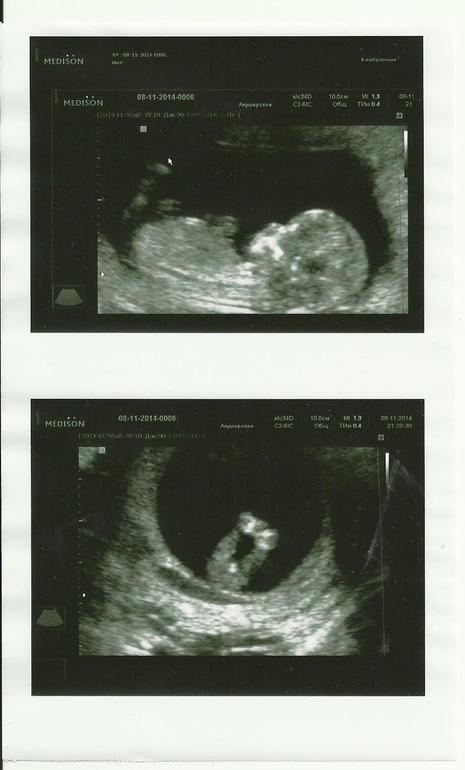

Вопросы про УЗИ, обследования и анализы: что, где, как, когда?12-13 неделя, пошли с мужем на УЗИ. С малышом все хорошо, он уже 61мм от головки до копчика, желудок, сердце, все косточки визуализируются. Сказали предварительно что скорее всего девочка, ну а там дальше видно будет (похоже мальчика никогда не дождемся). Но сколько же это эмоций, словами не передать. Я видела как малыш открывает ротик, как двигает ручками, ножками, выпрямляет спинку двигается очень много это было очень трогательно, все рассказали, все показали, где пяточки, где бедра с попкой, ротик, носик, пуповинку, все рассмотрела.

Вот такие наши попки и личико